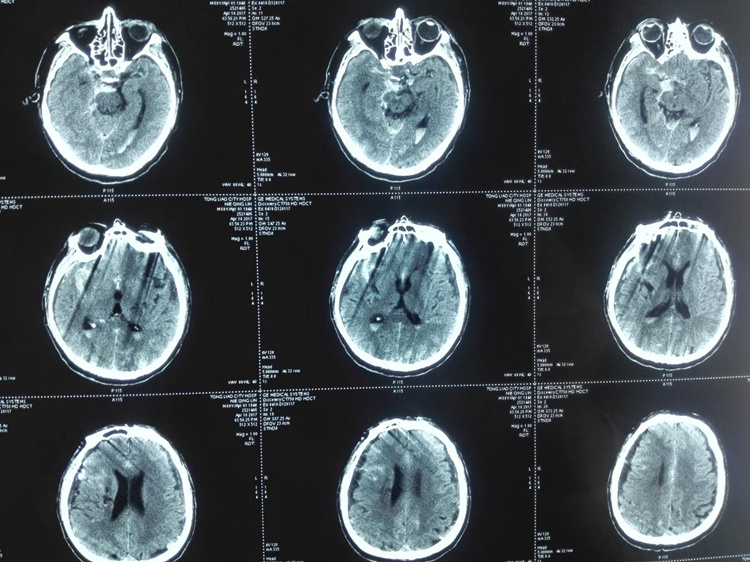

术前头颅CT

.jpg)